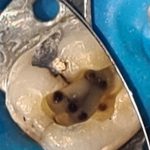

A paciente foi encaminhada já com o acesso realizado no dente 36, após o diagnóstico de pulpite aguda irreversível. Após a anestesia, isolamento do campo operatório e remoção da restauração provisória, foram encontrados cinco canais com auxílio da microscopia. Entre eles, o canal mésio-medial, na raíz mesial, e situado entre o canal mésio-vestibular e o mésio-lingual.

Todos os canais foram preparados com limpeza foraminal, utilizando o Reciproc Blue #25 após a localização foraminal eletrônica. O glide path foi realizado com lima manual #10.02. A solução irrigadora foi soro fisiológico e gel de clorexidina a 2% em todo o preparo e, antes da obturação, o uso de ativação ultrassônica da solução de EDTA.